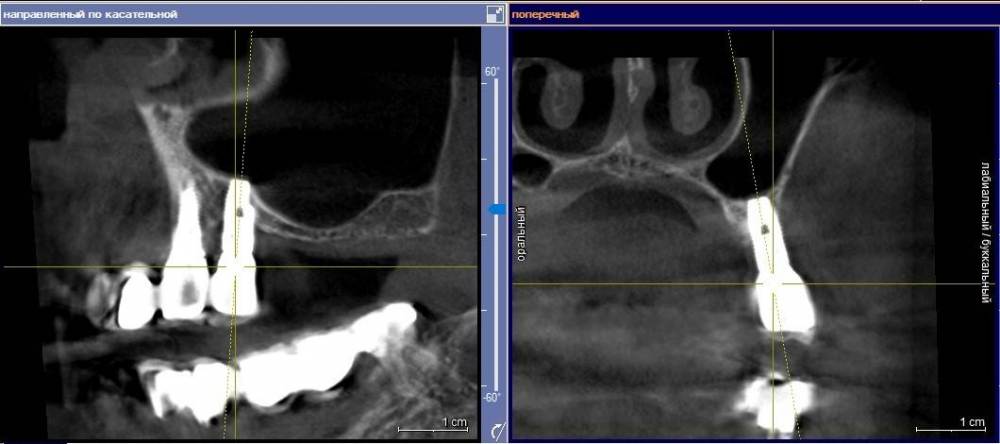

Ponchik Опубликовано 23 ноября, 2021 Поделиться Опубликовано 23 ноября, 2021 Заказ от начальства(ортопеда). Пациентка направлена ко мне со словами: вам сейчас косточки подсыпят, десенки пришьют и всё ок. Инересует второй сегмент, остальные и так ок. Работе всего пара лет. Делал не я. Импланты альфа-био. Прикреплёнки нет нигде. Всё хлюпает. Второй сегмент - я за удаление имплантов, через два месяца сунус+кость+мембрана(титан или полужесткая), через полгода 24, 26 импланты. Через 3 месяца мягкотканные дела, ещё через пару месяцев замаячит протезирование. (если всё остальное сложится) Как "подлепить" десну не снимая ортопедии, за два-три визита, хотя бы прикрыть витки? Я не знаю. Приму любой совет. Ссылка на комментарий

АнтонТЛТ Опубликовано 23 ноября, 2021 Поделиться Опубликовано 23 ноября, 2021 Витки заполировать и провести медикаментозную обработку. Но лучше конечно удалить такие имплантаты. Хорошо что в вашем случае нет зубов дистально) Ссылка на комментарий